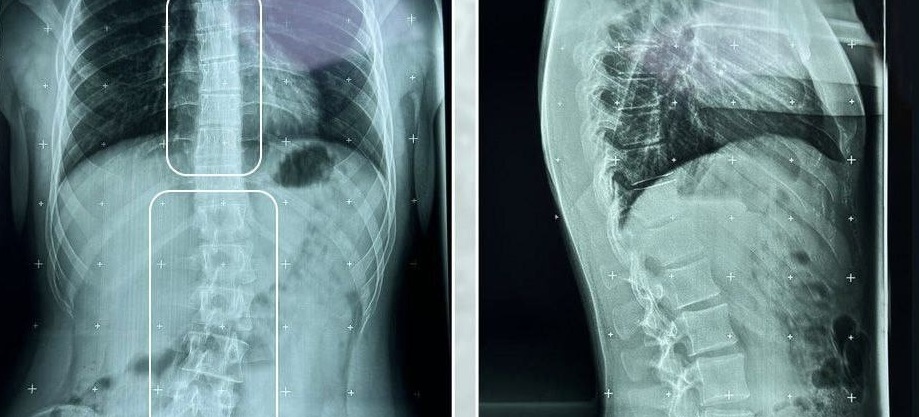

Кейс: сколиотическая деформация позвоночника

Пациент 17 лет обратился с жалобами на деформацию спины и периодическую, умеренную боль в поясничном и грудном отделах позвоночника.

Проведено дополнительное обследование — панорамная рентгенография позвоночника в двух проекциях. Диагностировано — сколиотическая деформация позвоночника на уровне грудного (левосторонняя дуга с углом 8°) и поясничного (левосторонняя дуга с углом 15°) отделов с осевой ротацией позвонков.

В соответствии с клиническими и рентгенологическими данными пациенту рекомендован курс реабилитации (массаж, физиопроцедуры, занятия с физическим терапевтом). Не пренебрегайте профилактическими осмотрами — они сохранят ваше время и здоровье.